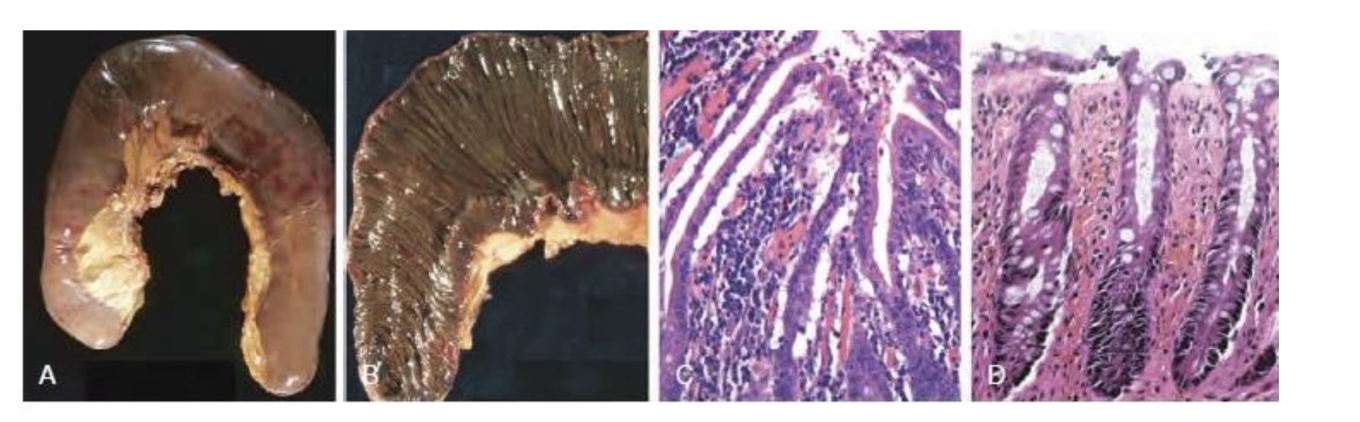

ENFERMEDAD ULCEROSA PÉPTICA (ÚLCERA CRÓNICA)